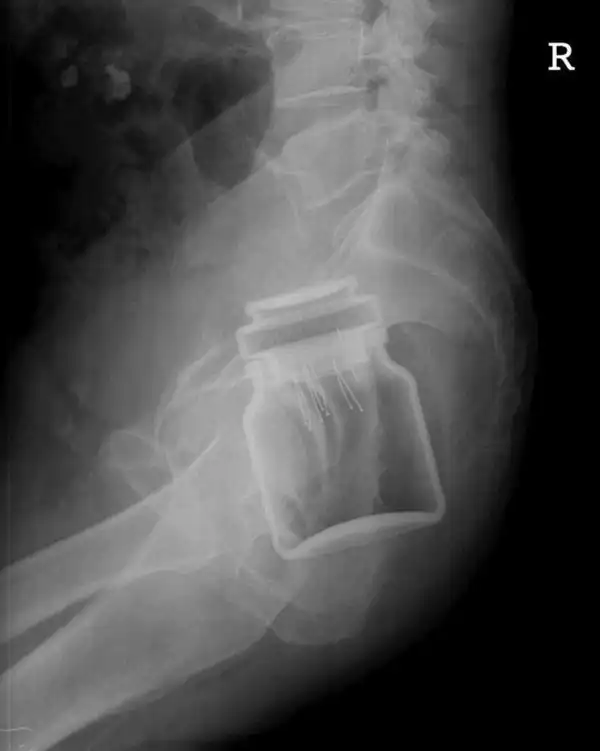

Врачебные находки в интимных местах

Или как впихнуть невпихуемое :lol: